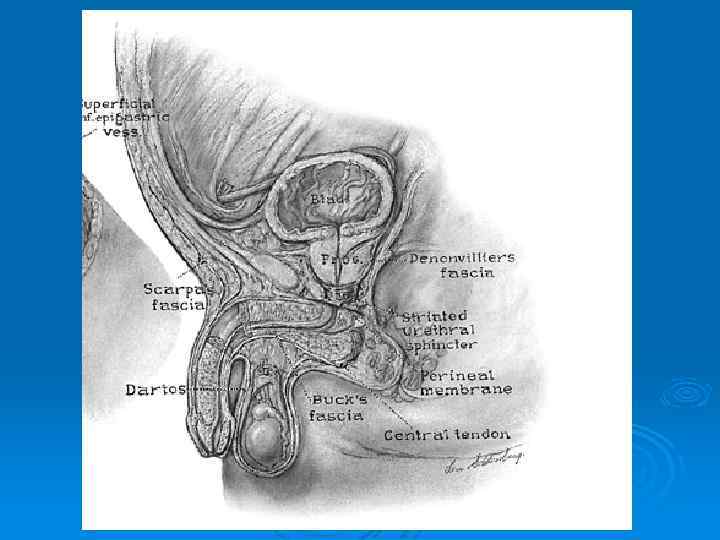

Фертильность: 1. Нарушения сперматогенеза Сосудистая патология Воспалительная патология Пороки развития яичка и придатка Иммунный конфликт Последствия травмы и ишемии яичка 2. Патология транспорта Обструктивное бесплодие Механическое бесплодие Пороки развития 3. Эректильные нарушения 4. Копулятивные нарушения Искривления пениса Гипоспадия Эписпадия Микропенис Скрытый половой член Пеноскротальная транспозиция 5. Опухоли